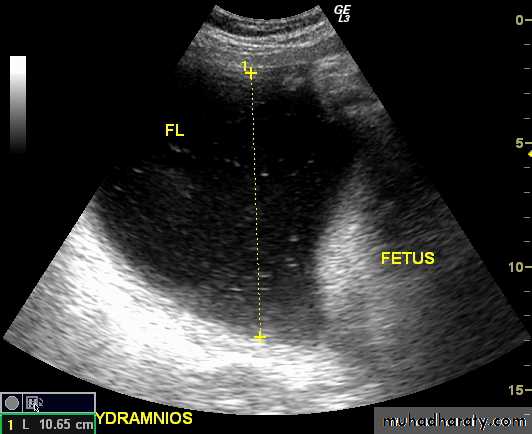

Poly hydraminous :

Poly hydraminos refers to a situation where the amniotic fluid volume is more than expected for gestational age.It is generally defined as:

amniotic fluid index (AFI) > 25 cm

largest fluid pocket depth (maximal vertical pocket (MVP)) greater than 8 cm

overall amniotic fluid volume larger than 1500-2000 cc3